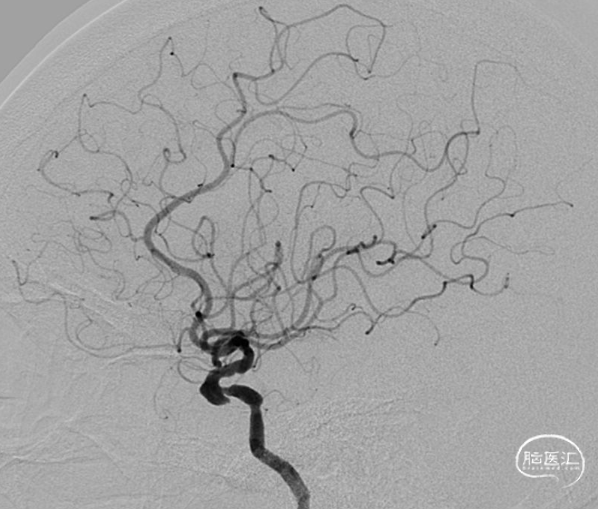

术前影像

脑血管造影(主动脉弓造影及后循环)

右侧颈动脉造影

左侧颈动脉造影

左侧颈内动脉重建(左侧狭窄及扩张较右侧更甚)